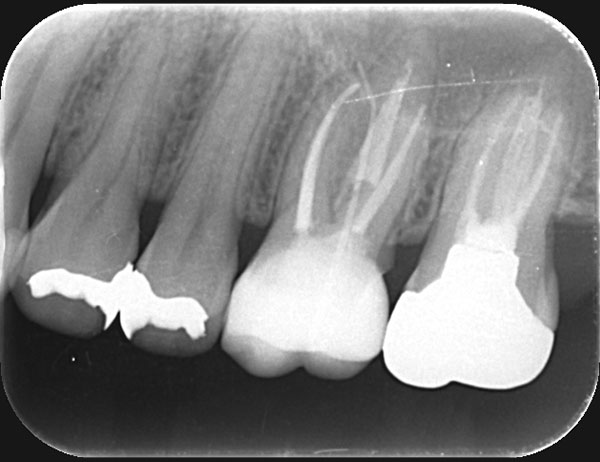

術前

術後

症例について

主訴:

硬いものを食べると違和感があり疲れたら歯が浮いてる様な感じがする

治療内容:

過去に行った根管治療をやり直し、再感染の原因を取り除く治療です。

治療期間:各90分 2回

費用:クラウンコア除去 5,500円(税込)/ 隔壁形成 5,500円(税込)/ 再根管治療 132,000円(税込)/ 築造 16,500円(税込)

治療に関わるリスクまたは副作用:

症状が改善しない場合、外科的歯内療法または抜歯が必要になることがあります。